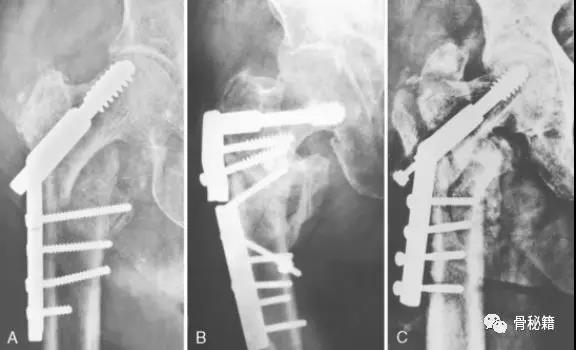

一个双膦酸盐治疗5年的患者粗隆下非典型骨折

采用了髓内钉固定,术后一年内固定失效

更换了DCS+植骨固定,术后四个月又发现了内固定失效再次更换了更长的DCS

这次的固定能成功吗?